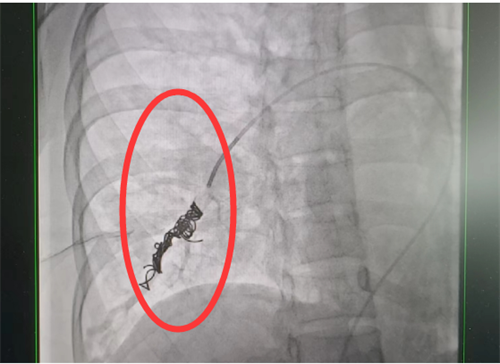

外周血管介入科进行介入手术治疗。此类手术难度大,风险高,经科室团队仔细讨论,定下最佳方案,为患者顺利实施了肺动静脉瘘封堵术,手术全程4小时,术后平稳回到病房。术后复查肺动静脉瘘已消失不见,经过后续的对症治疗和护理,梁瑶恢复良好,于5月上旬出院。

栓塞术后造影